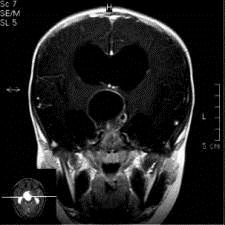

病历摘要:??患者女性,6岁,半年来感觉视力模糊,近10天出现反复头痛,间有恶心呕吐,精神转差,查体:神志清楚,身高90cm,体重25Kg,血压90/55...

问题 病历摘要:??患者女性,6岁,半年来感觉视力模糊,近10天出现反复头痛,间有恶心呕吐,精神转差,查体:神志清楚,身高90cm,体重25Kg,血压90/55mmHg,右眼视力4.6,左眼视力4.8,双侧视乳头水肿,颈软,伸舌居中,四肢肌张力正常,肌力5级,双侧Babinski征(-)。 患者术后第三天,神志逐渐转差,浅昏迷状态,并出现癫痫大发作,体查:颈抵抗,HR110次/分,T38.5℃,BP90/52mmHg,中心静脉压10mmHO,右侧瞳孔2.5mm,光反射迟钝,左侧瞳孔2.0mm,光反射灵敏,刺痛右侧肢体可以定位,左侧肢体见轻微肌肉收缩动作,右侧Babinski征(-),左侧Babinski征(+)。考虑患者病情加重的最可能原因有?

选项 A.高渗性昏迷 B.低渗性昏迷 C.水中毒 D.感染性休克 E.缺血缺氧性脑病 F.脑血管痉挛 G.脑梗塞 H.脑出血 I.无菌性脑膜炎

答案 GH